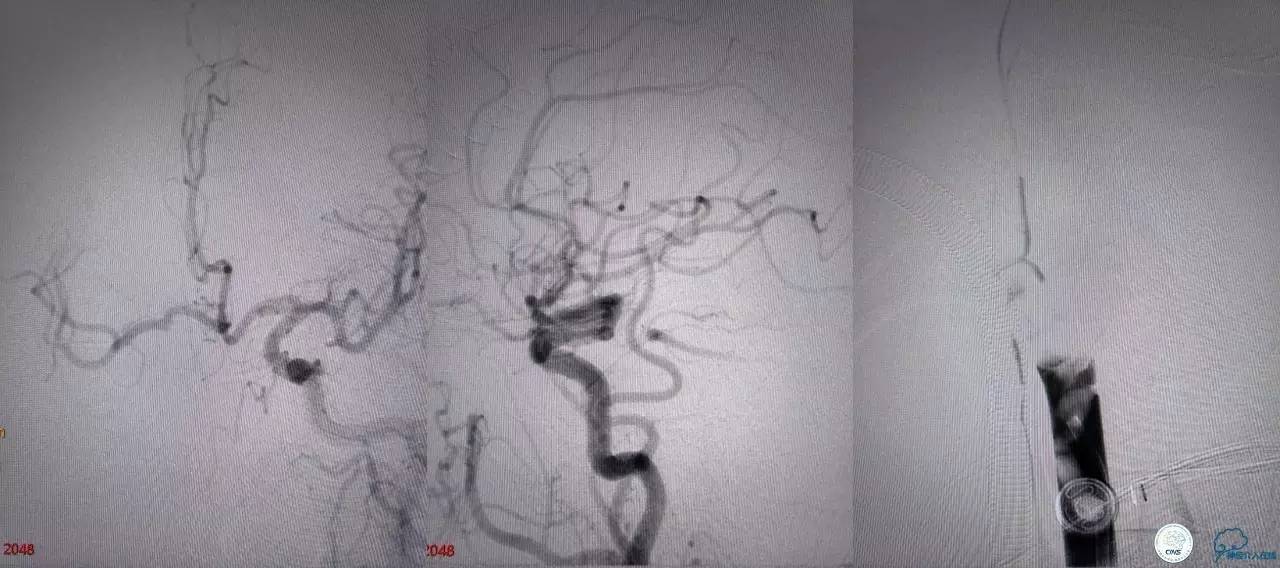

基底动脉顶端仍有大量血栓,双侧大脑后动脉未见显影,双侧小脑上动脉再通。再次取栓?还是动脉溶栓?

决定导管内给予替罗非班6ml,复查造影BA顶端仍闭塞,第二次取栓。

第二次取栓后可见基底动脉顶端仍有大量血栓,右侧大脑后动脉开通,但左侧大脑后未见显影且左侧小脑上动脉闭塞!

第三次取栓,支架放入左侧大脑后取栓。

第三次取栓后,左侧大脑后动脉开通,但是栓子再次栓塞右侧大脑后动脉,血栓在基地动脉顶端来回左右摆动,下一次,怎办?血栓负荷太多,可以使用solumbar技术,可以没有颅内导管,没办法,换用更大的支架6-20mm,但费用增加不少,与家属沟通后同意使用,第四次取栓: